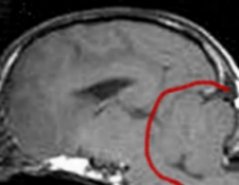

Above is shown a comparison of an MRI showing a full cerebellum

vs. the skull X-RAY of a dog with a full cerebellum and a dog

with an MRI showing a crushed cerebellum vs. the skull X-RAY of

a dog with a crushed cerebellum. The cerebellum is circled in

red. You can easily see there is a huge difference in shape of

cerebellum between these two dogs--the one on the left is quite

full, the one on the right is severely crushed.